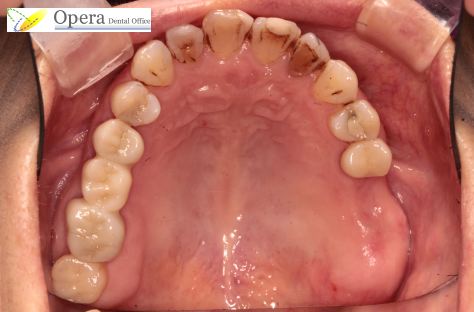

術前です。

これに保険で入れ歯を入れようとすると下の図の様になり、たった2本のために天井の間隔が非常に悪いものとなってしまいます。